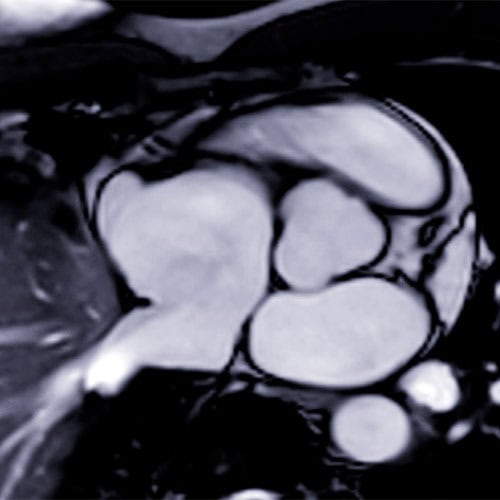

DPC et JESFC